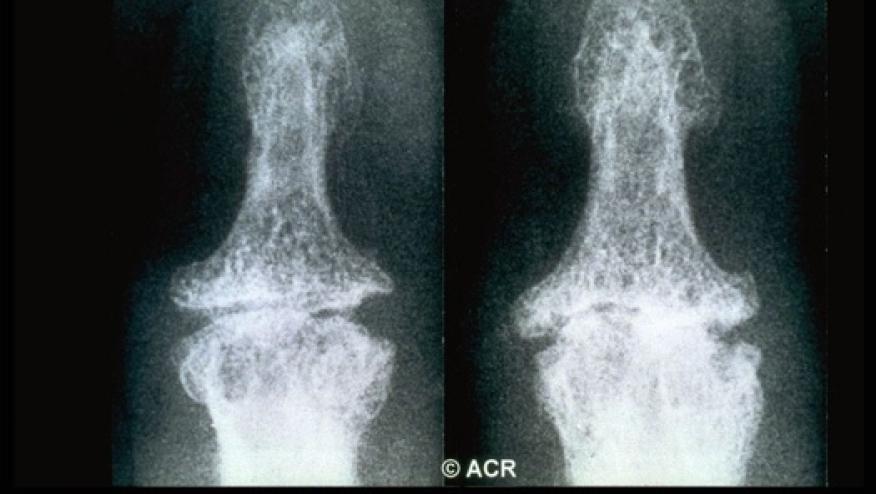

A point-based classification system is based on age, duration of morning stiffness, number of joints with osteophytes and joint space narrowing, and concordance between symptoms and radiographic findings. To be classified (diagnosed) the following cut-offs were proposed:

- Number of joints (DIPs, PIPs, IP1, CMC1) with osteophytes: None=0; 1–2 joint(s)=2; 3–5 joints=3; 6 or more=4

- Number of joints (DIPs, PIPs, IP1, CMC1) with Joint space narrowing: None=0; 1–2 joint(s)=1; 3–5 Jts=2; 6 or more=3